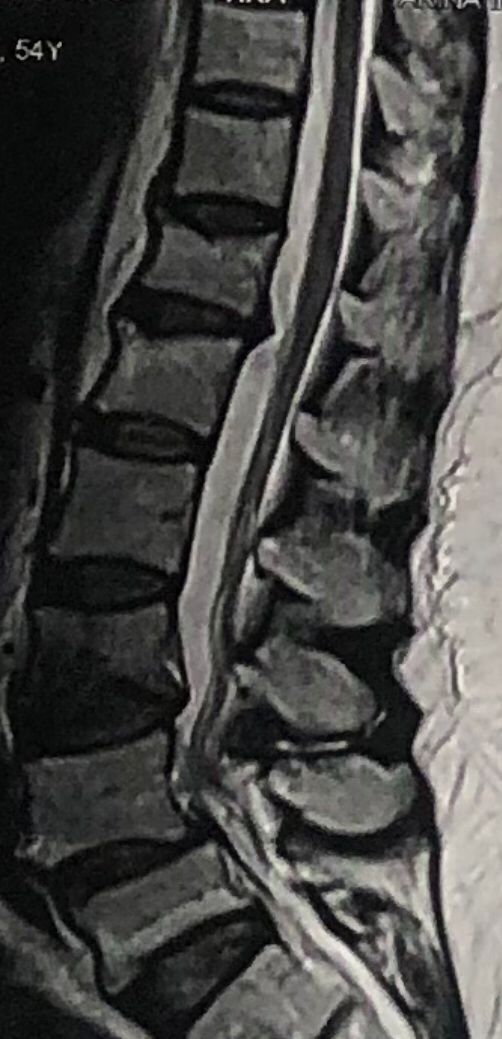

70 yrs old female presented to my clinic today (Oct 06/2024)due to severe LBP with both legs pain for several years.

7 years ago came to my clinic with L leg radicular pain and I referred her to a neurosurgeon. Patient underwent full laminectomy from L1 to S1. Few months after surgery her LBP and legs pain were started and hasn’t improved since then. Now walking aggravates the pain and forces her to bend forward. Patient had mri from 6 months ago. Her mri 7 years ago was similar to the recent mri, just laminectomy and soft tissue collection has been added. In neurological examination p.tvdid not have any neurological deficits. I ordered lower limbs emg/ncv, dynamic lumbar spine X.ray. As a chiropractic Doctor what would be your plan of management for this patient?